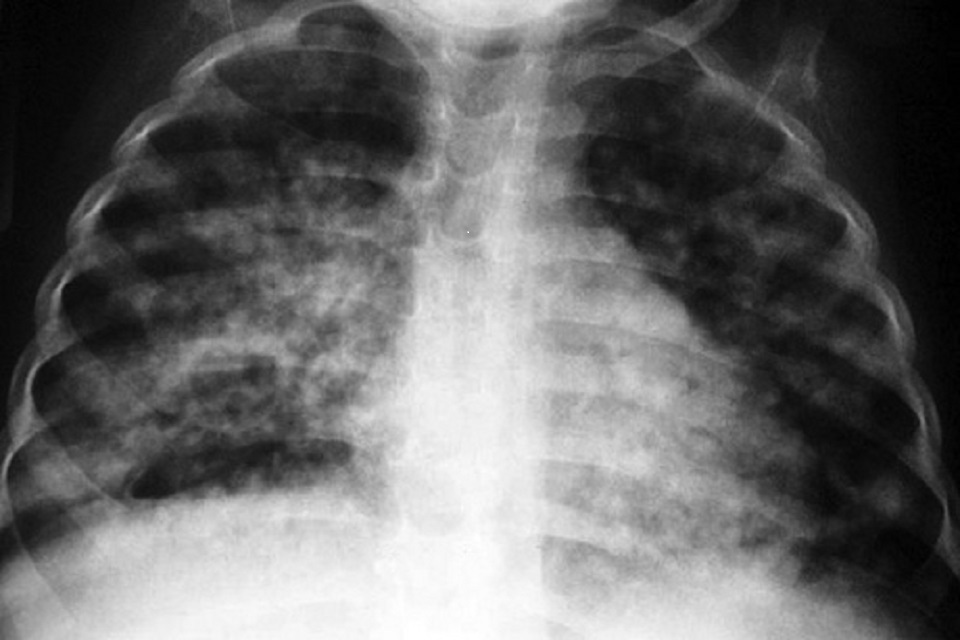

Progress towards TB elimination has stalled

Although England continues to be a low incidence country for tuberculosis (TB), decline in rates has levelled off.

Despite an overall downward trend in the number and rate of TB notifications in England during the last 10 years, the rate of decline has slowed in the last 4 years. Unless immediate action is taken, England will fall short of achieving the World Health Organization (WHO)’s End TB Strategy target of 90% reduction in people with TB from 2015 to 2035.

In 2021, the incidence of TB stood at 7.8 notifications per 100,000 people, compared to 8.4 notifications per 100,000 in 2019. Although this is a decline since before the pandemic, in order to hit the WHO elimination target by 2035, we need to see a reduction in TB rates to 1.05 per 100,000. If we continue at the current rate of decline, we will only hit 5.1 per 100,000 by 2035. Provisional data from 2022 indicates we remain off trajectory.